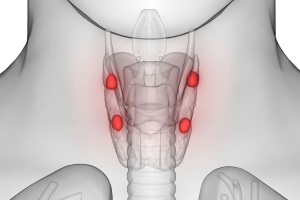

Первинний гіперпаратиреоз – захворювання, розвиток якого пов’язаний з надлишковою секрецією ПТГ пухлиннозміненими або гіперплазованими ПЩЗ.